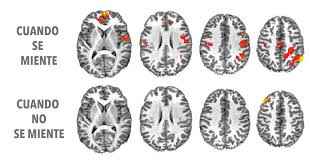

Una de las autoras del estudio, la Dra. Tali Sharot, profesora asociada de neurociencia cognitiva en University College London,piensa que la desactivación de la amígdala (el área del cerebro que responde emocionalmente cuando se miente) propicia a la deshonestidad y ayuda a la persona que miente.